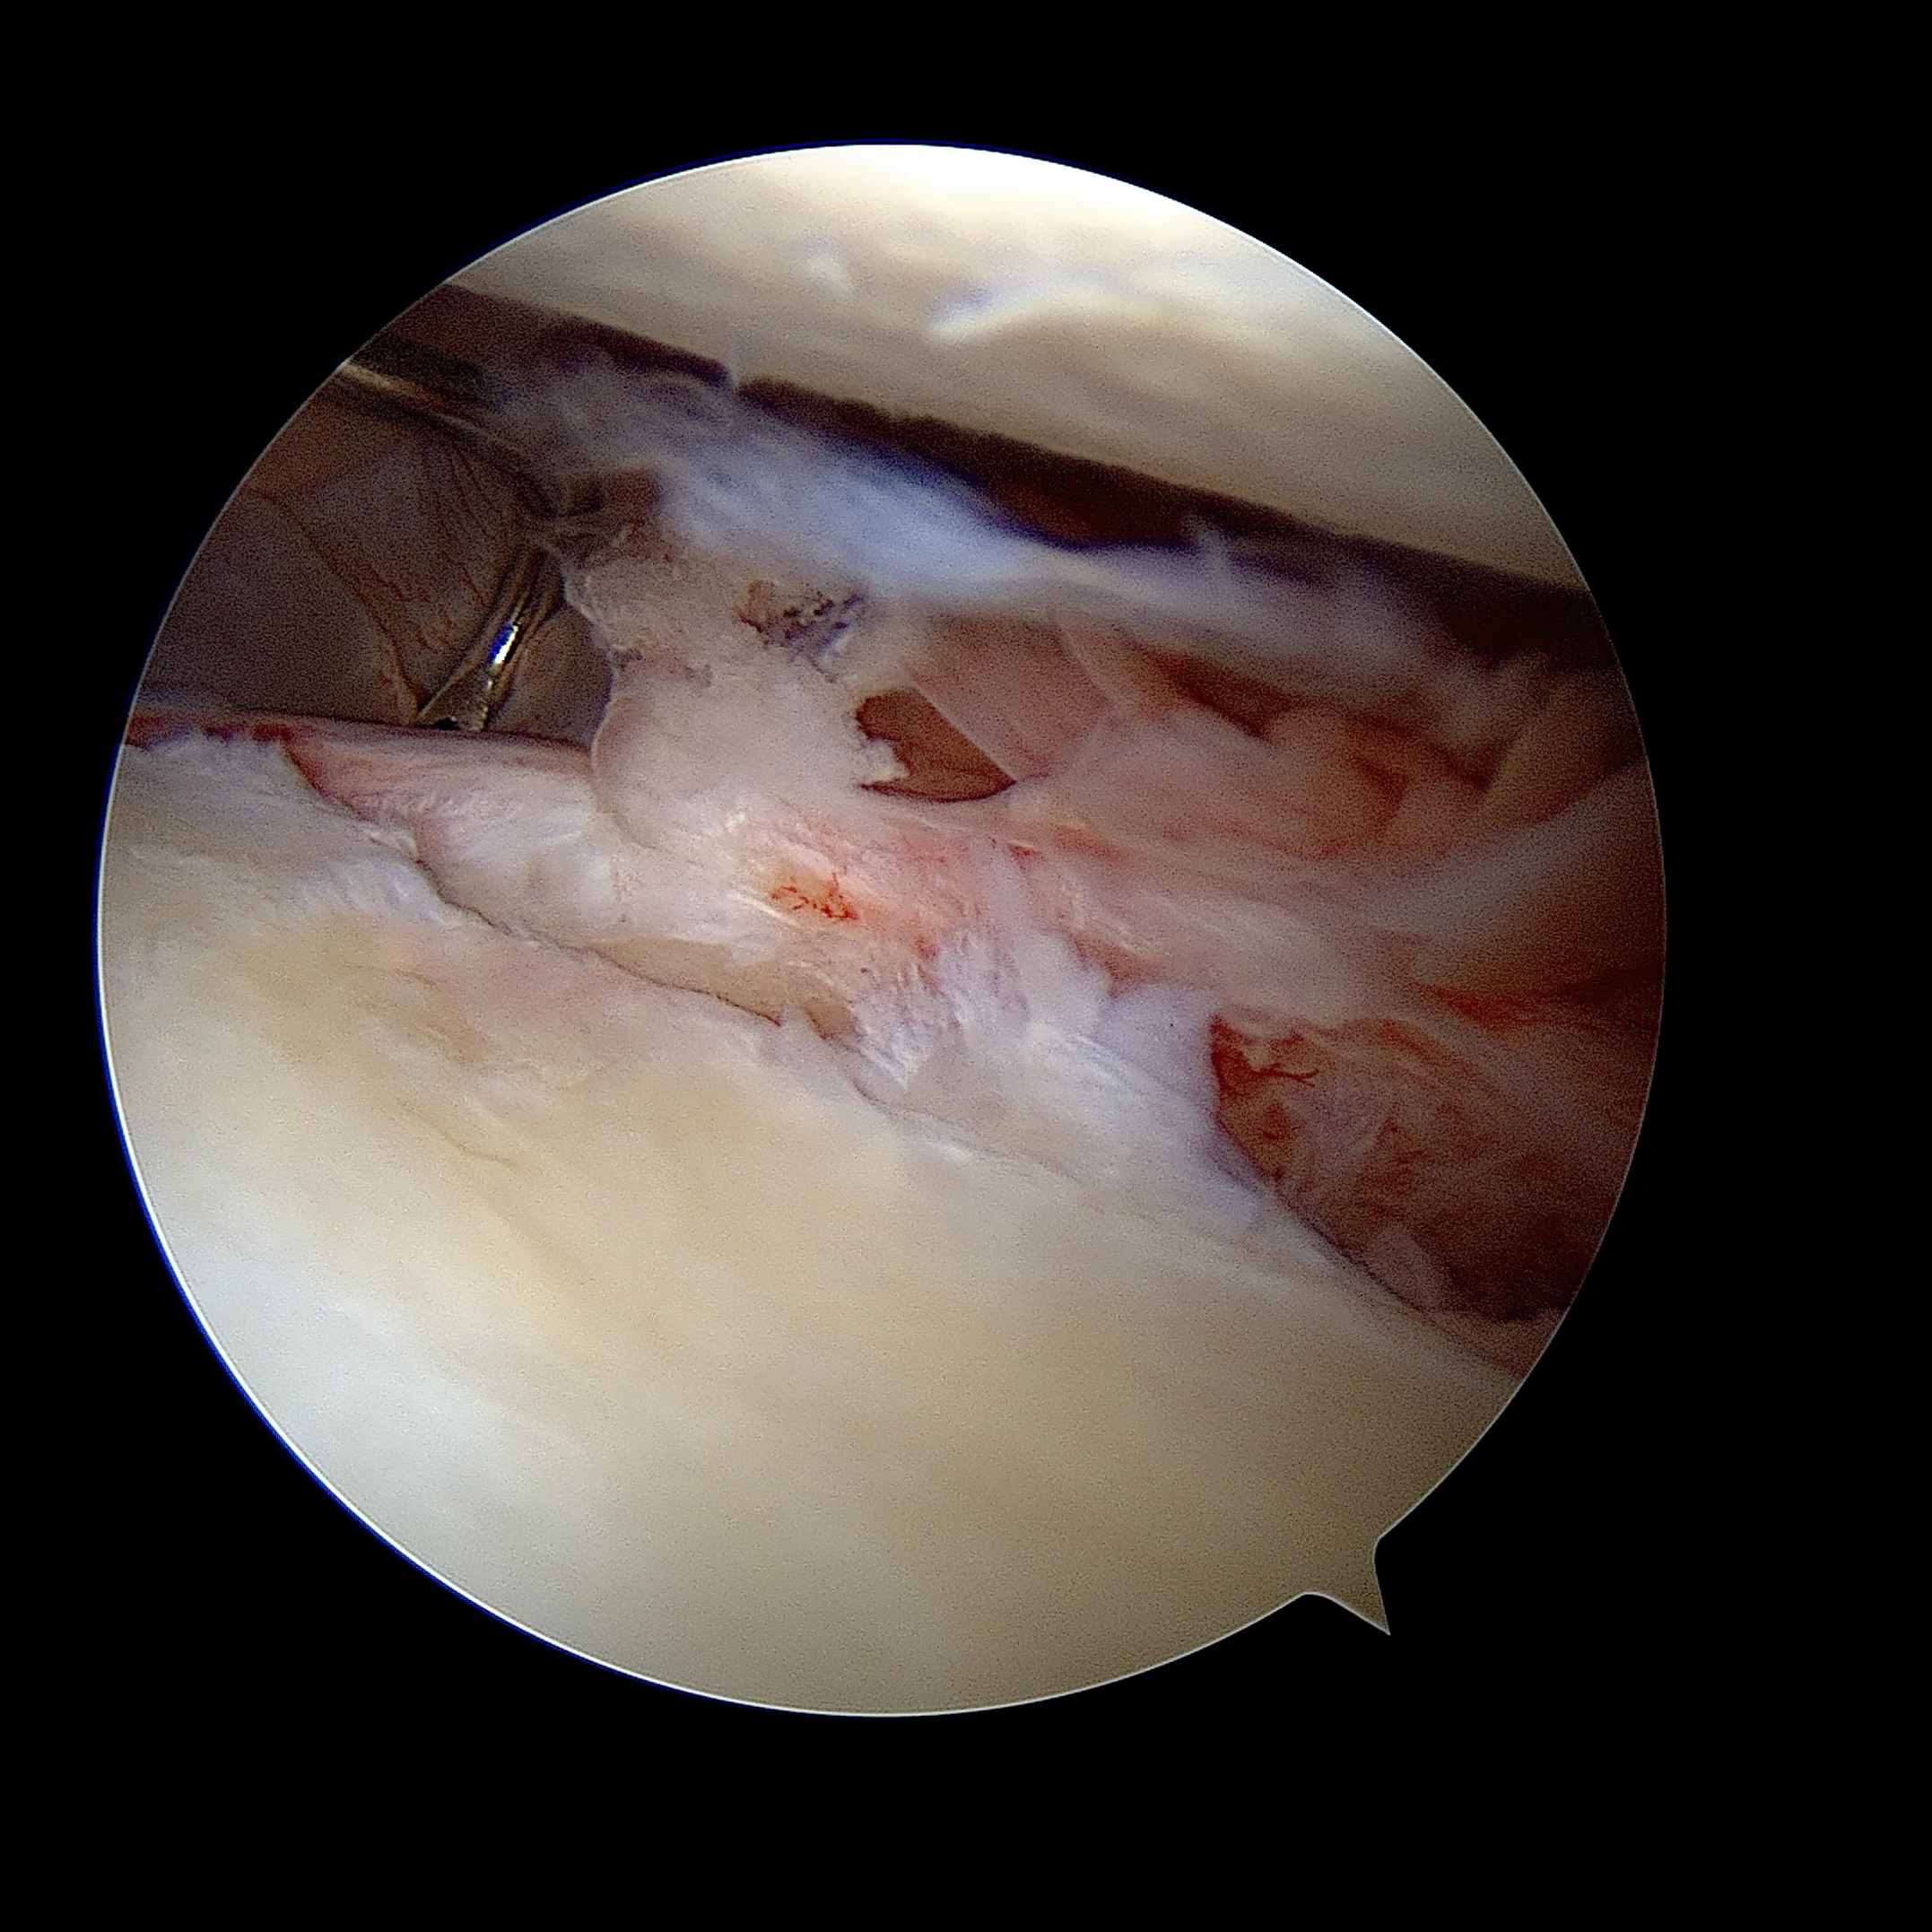

Comment ? L'intervention est réalisée entièrement sous arthroscopie (vidéochirurgie), par 2 à 3 incisions de quelques millimètres seulement. Le labrum arraché est réinséré sur la glène à l'aide d'ancres résorbables sur lesquelles sont fixés des fils très résistants. Les ligaments gléno-huméraux distendus sont retendus dans le même temps opératoire.

Le remplissage de l'encoche postérieure (Hill-Sachs remplissage)

Pour qui ? En complément du Bankart, quand l'encoche humérale postérieure est engageante.

Comment ? L'encoche est comblée en plicaturant la coiffe des rotateurs dans le défect osseux à l'aide d'ancres miniaturisées. Cette technique arthroscopique évite dans certains cas de recourir à une butée.

Le Bankart postérieur

La réinsertion du bourrelet glénoïdien (technique de Bankart) est réalisée aujourd'hui sous arthroscopie (vidéochirurgie) en faisant 2 ou 3 petites incisions de quelques millimètres. L'objectif est de retendre les ligaments distendus de l'épaule et de refixer le bourrelet glénoïdien à l'aide d'ancres (le plus souvent résorbables) sur lesquelles sont fixés des fils très résistants.